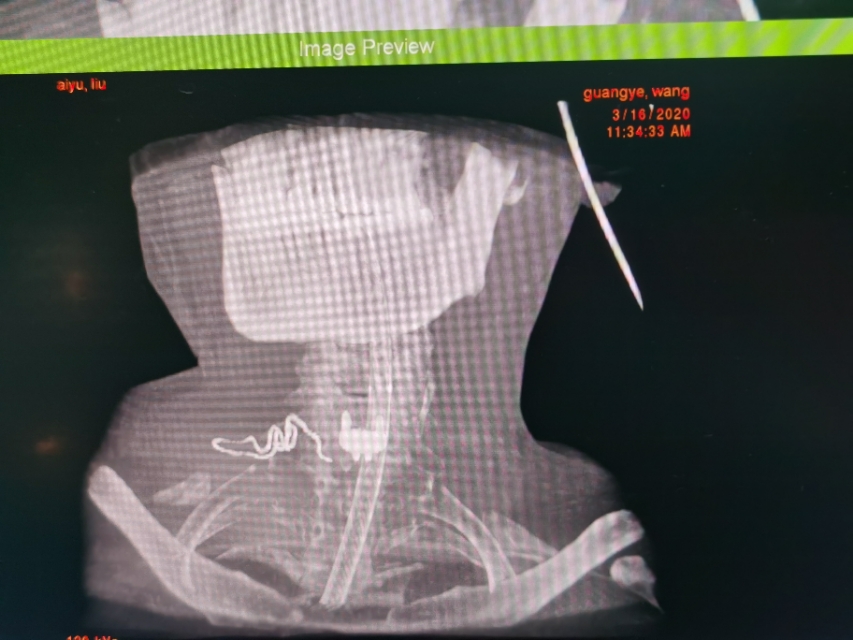

中年人疫情期居家长期卧床及长期看电脑手机,颈椎病复发今天显微镜下微创治疗,颈6-7巨大椎间盘突出.压迫神经根管,伴左上肢剧烈放射痛,显微镜下微创颈椎间盘突出治疗,用时半个小时,近零出血,取出压迫神经4块髓核,切除后纵韧带,减压至脊髓表面,脊髓恢复正常搏动,神经监护神经功能恢复好